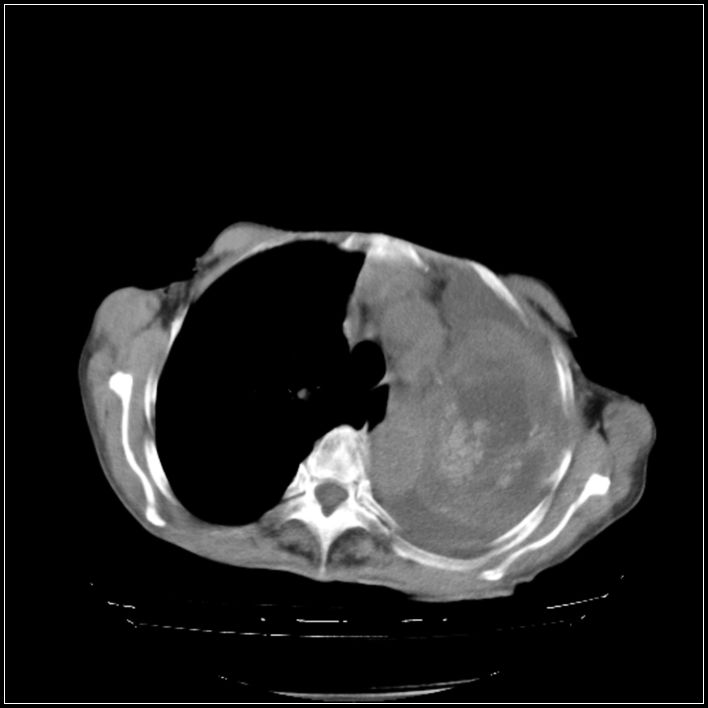

以下是引用ydx_74在2008-5-31 16:08:00的发言:[br]中心性肺癌并左侧肺不张、胸水。